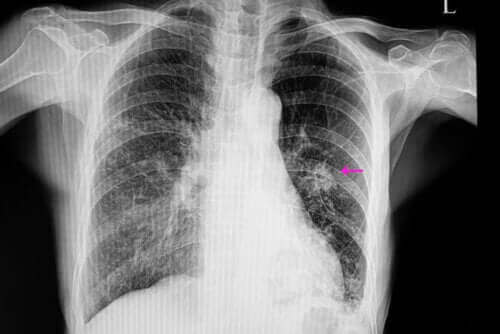

В такива случаи, възлите ще имат необичаен външен вид със слабо формирани ръбове; това се вижда при рентгеновото изследване. Също така, те обикновено са по-малки от доброкачествените. Освен това, те са част от определени рискови фактори като:

Рентгеновото изследване може да засече белодробен възел.

Щом това е направено, лекарят трябва да извърши определени образни изследвания за да се засече възела. Освен това, изображенията ще му позволят да прегледа определени характеристики като форма и размер. Това е така защото те са важни за различаване на доброкачествен възел от злокачествен.

Най-често срещаните начини за тяхното диагностициране са чрез рентген на гръдния кош и компютърна томография. За да разберете точната причина за белодробен възел, лекарите правят биопсии понякога, тъй като те им позволяват да анализират тъканите.